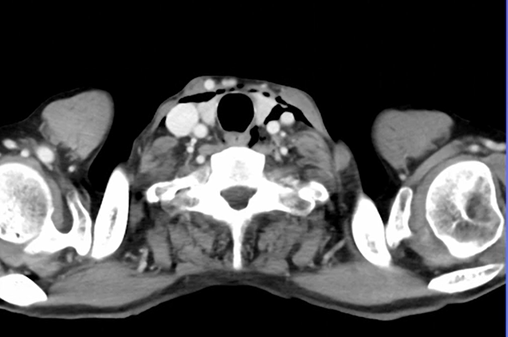

左胸痛が続くため造影CT施行。

所見:

前頚部に気腫、食道周囲に気腫、わずかに気胸も見られる。左胸水も見られる。

特発性食道破裂が最も疑われる症例。